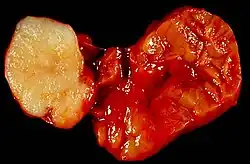

Pleomorphic adenomaCoronal MRI showing right parotid adenoid cystic carcinoma.

Benign tumour of the submandibular gland, also known as pleomorphic adenoma, presented as a painless neck mass in a 40-year-old man. At the left of the image is the white tumour with its characteristic cartilaginous cut surface. To the right is the normally lobated submandibular salivary gland.Warthin's tumor